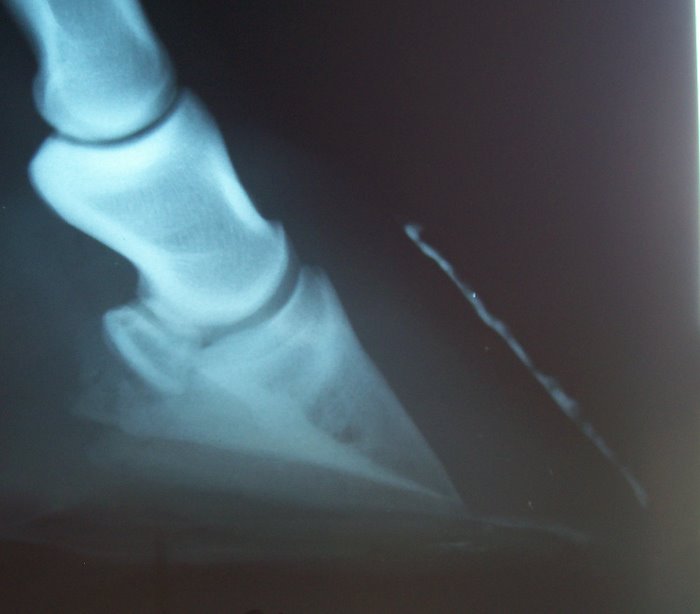

Here are his x-rays from 2007 a couple mos. after founder.

Here are x-rays from late April of this year

I don't know if that might help or not.

I agree with the comments about him looking like he's bearing too much weight on his sole. Also, looking at the x-rays, it looks like he may be somewhat out of balance and need more trimmed off one side, but I can't tell how the x-rays are labeled so am not sure which side. But, see how in the x-ray when looking at the bottom of the coffen bone you can see a shadow of the other side of the bone? (am I making myself clear?) The bottom of the bone should look straight across when the x-ray is taken from the side, with no shadow of the other side. A good way to tell about balance for sure is to get an x-ray that shows the two little holes where arteries go in the back of the hoof. (Sorry, I can't think what they are called.) If you go to https://www.horseadvice.com/horse/messages/21/15752.html there is an x-ray of the hoof and you can see these two "holes" above the blue line. On an x-ray you should be able to run a totally straight line between bisecting these two "holes." If you can, the horse is in balance laterally. This is according to a specialist (a vet who only deals with legs and feet)that I took one of our horses to.